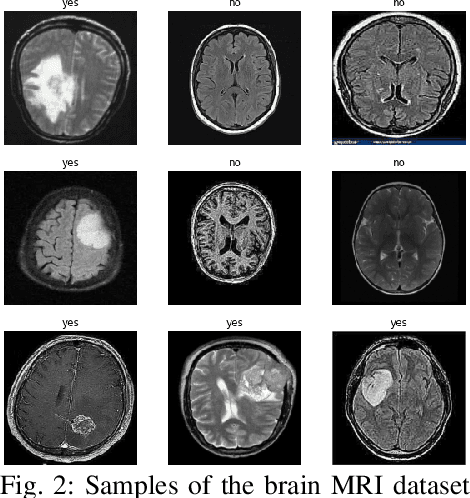

Abstract:Uncontrolled cell division in the brain is what gives rise to brain tumors. If the tumor size increases by more than half, there is little hope for the patient's recovery. This emphasizes the need of rapid and precise brain tumor diagnosis. When it comes to analyzing, diagnosing, and planning therapy for brain tumors, MRI imaging plays a crucial role. A brain tumor's development history is crucial information for doctors to have. When it comes to distinguishing between human soft tissues, MRI scans are superior. In order to get reliable classification results from MRI scans quickly, deep learning is one of the most practical methods. Early human illness diagnosis has been demonstrated to be more accurate when deep learning methods are used. In the case of diagnosing a brain tumor, when even a little misdiagnosis might have serious consequences, accuracy is especially important. Disclosure of brain tumors in medical images is still a difficult task. Brain MRIs are notoriously imprecise in revealing the presence or absence of tumors. Using MRI scans of the brain, a Convolutional Neural Network (CNN) was trained to identify the presence of a tumor in this research. Results from the CNN model showed an accuracy of 99.17%. The CNN model's characteristics were also retrieved. In order to evaluate the CNN model's capability for processing images, we applied the features via the following machine learning models: KNN, Logistic regression, SVM, Random Forest, Naive Bayes, and Perception. CNN and machine learning models were also evaluated using the standard metrics of Precision, Recall, Specificity, and F1 score. The significance of the doctor's diagnosis enhanced the accuracy of the CNN model's assistance in identifying the existence of tumor and treating the patient.